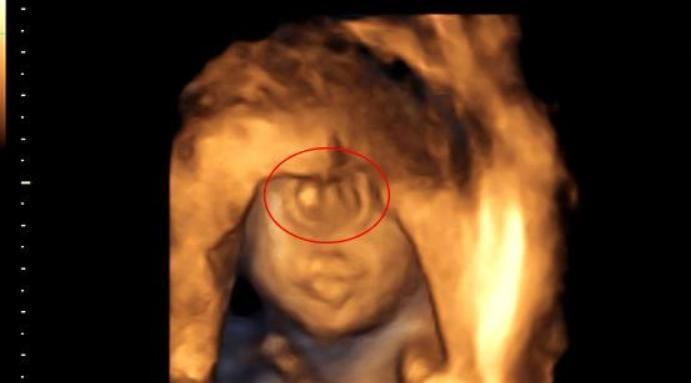

可是,不幸的事还是来了,李女士的宝宝出生后眼睛一直没睁开,检查后才发现,原来宝宝先天视力就有问题,而这个关于眼睛的缺陷,产检是看不出来的。

像李女士宝宝的情况,就属于先天性的视力异常,而且大部分无法治愈。因为胎儿在腹中时,不会睁开眼睛,出生后也需要一段时间睁开眼睛,所以,宝宝的视力问题,只能通过后天检查。

有调查显示,0到10岁的孩子,如果视力有问题,一半以上都是天生的,因为产检无法检测宝宝的眼球是否正常,无论是B超还是核磁都不行。

3、指端异常

简单说就是宝宝多指缺指的问题,原则上宝宝如果有指端异常的问题,做B超是能看出来的,但现实中的B超清晰度太低,如果宝宝是握拳的姿势,根本看不到他们的手指和脚趾,就算是三维和四维也不行。